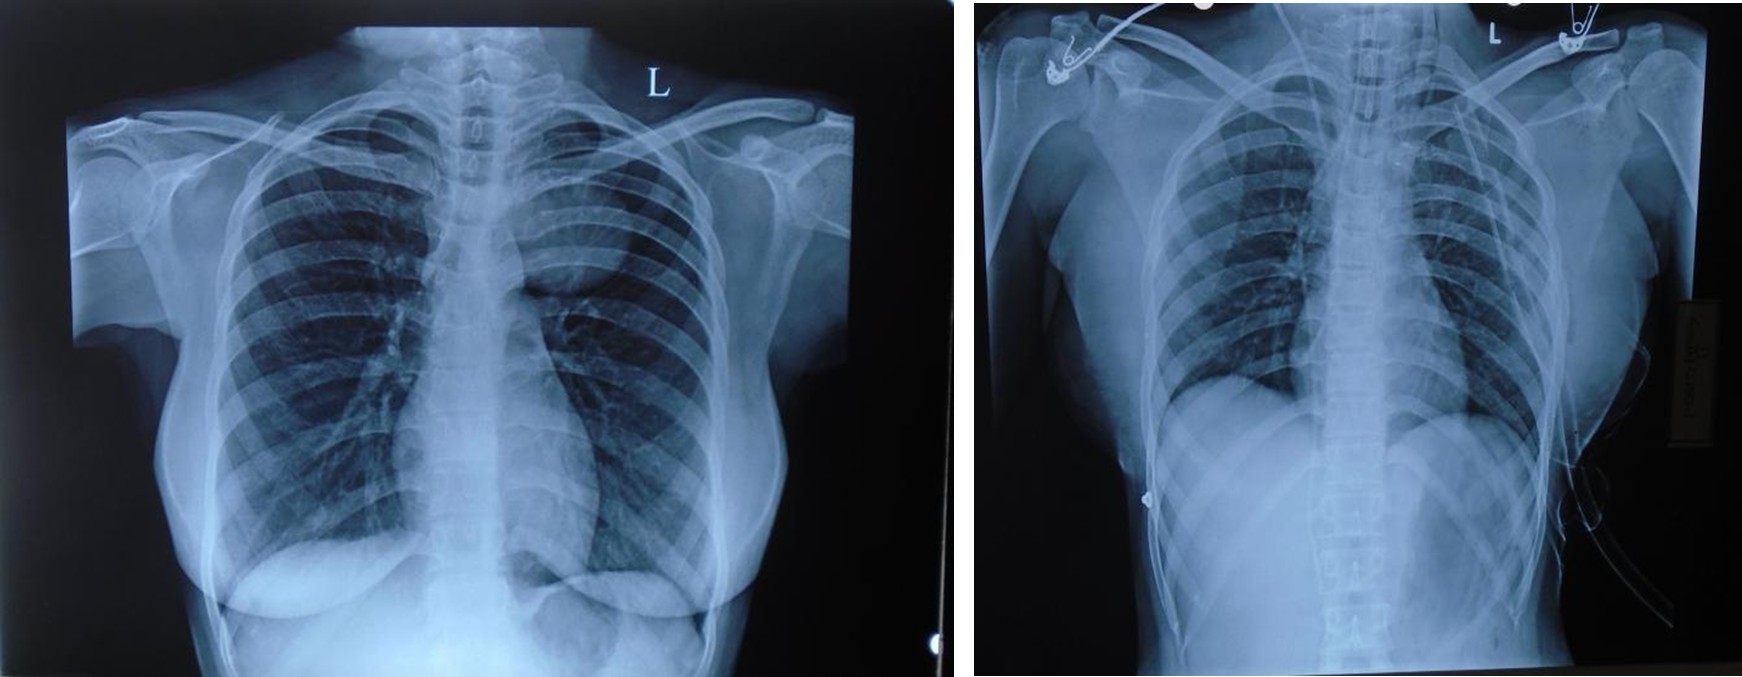

X-Ray

Before After